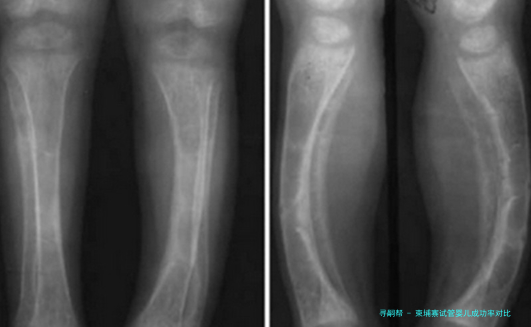

柬埔寨试管婴儿成功率相比

目前第三代试管婴儿技术成功率比较高的国家即是美国,可达百分之八十五左右,但是其费用同样是比较高的;柬埔寨试管婴儿成功率大概是60%左右,相比较美国而已,是要低一些的。